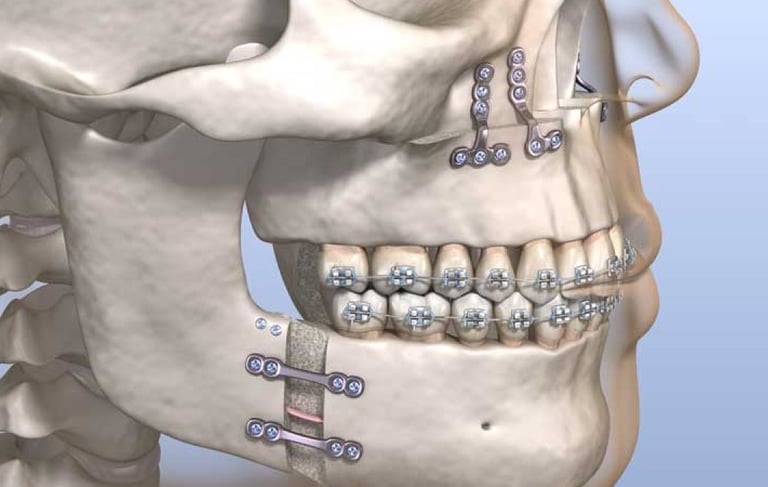

Es la corrección quirúrgica de deformidades de los maxilares para mejorar la función masticatoria, la apariencia facial y la salud dental. Incluye la realineación de la mandíbula y el maxilar para una mordida adecuada.

Cirugía ortognática